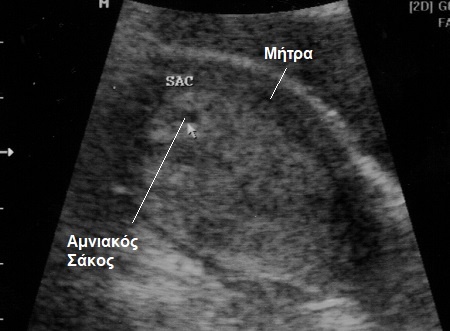

Σε γενικές γραμμές, θα πρέπει να μπορούμε να δούμε σάκο μέσα στη μήτρα – χωρίς όμως αυτό να είναι απόλυτο – όταν τα επίπεδα της χοριακής υπερβαίνουν τις 1000 IU/ml.

Τότε ο σάκος θα φανεί σαν ένας μικρός μαύρος κύκλος μέσα στη μήτρα σας (βλ. εικόνα).